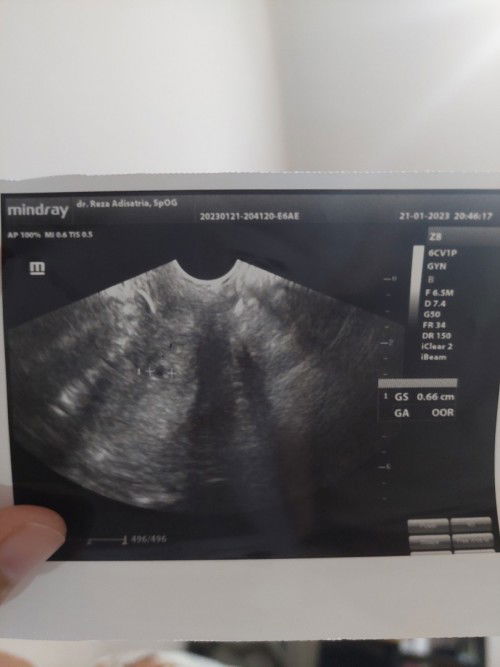

Hasil usg hpht 10des harusnya 6 week

Hai bun. Aku hpht 10 des, harusnya sekarang sdh 6w1d. Tapi kemarin flek dan usg transvag dokter bilang bs ada indikasi keluar (terburuknya) tp gak ada yg gak mungkin kalau allah berkehendak utk janinku berkembang. Ternyata pagi tadi sampai malam ini aku pendarahan spt mens disertai kram perut bawah yg luar biasa sakitnya, sampai kakiku lemes. Ada yg mau sharing mungkin yg pernah ngerasain? #usg6minggu #usg6weeks #keluarflek #pendarahan #ingintahu #bantusharing #firstmom #firstbaby